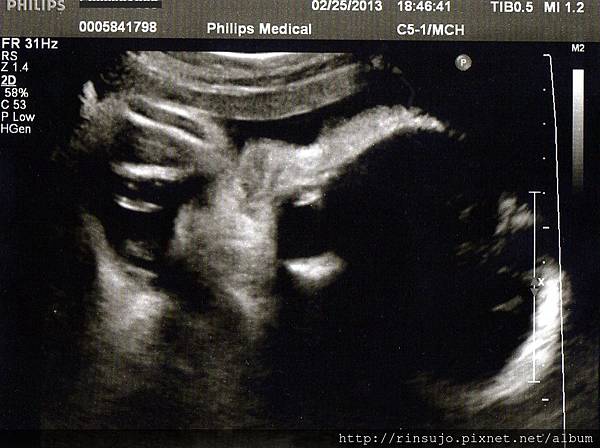

(32w2d產檢超音波)

32周產檢,小湯哥的體重已經是2171g,媽媽整個孕期重了5公斤

倒是小湯哥的重量一直維持在高標,完全不用擔心他吸收不良